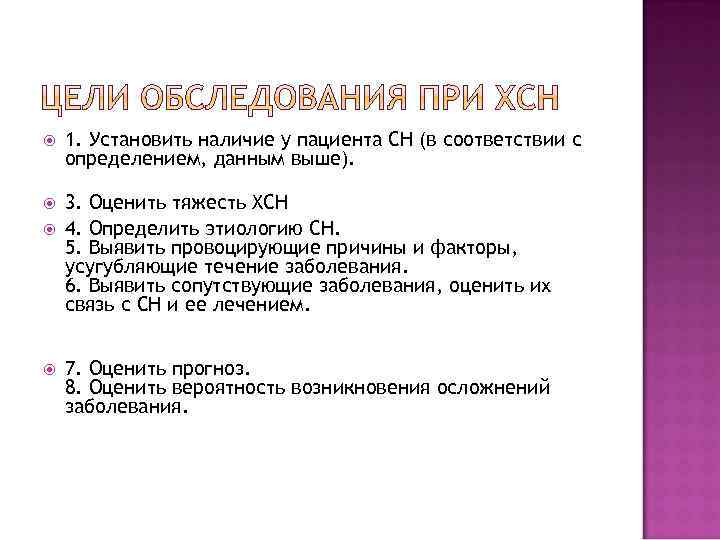

1. Установить наличие у пациента СН (в соответствии с определением, данным выше). 3. Оценить тяжесть ХСН 4. Определить этиологию СН. 5. Выявить провоцирующие причины и факторы, усугубляющие течение заболевания. 6. Выявить сопутствующие заболевания, оценить их связь с СН и ее лечением. 7. Оценить прогноз. 8. Оценить вероятность возникновения осложнений заболевания.

1. Установить наличие у пациента СН (в соответствии с определением, данным выше). 3. Оценить тяжесть ХСН 4. Определить этиологию СН. 5. Выявить провоцирующие причины и факторы, усугубляющие течение заболевания. 6. Выявить сопутствующие заболевания, оценить их связь с СН и ее лечением. 7. Оценить прогноз. 8. Оценить вероятность возникновения осложнений заболевания.